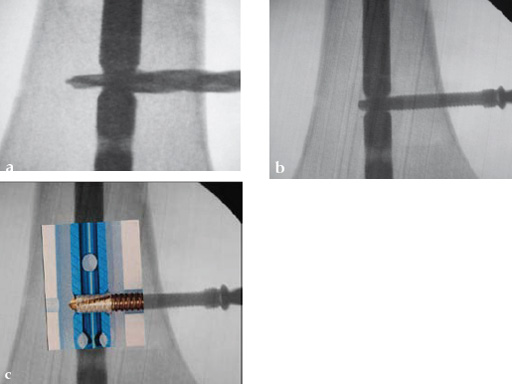

Drilling is identical but the near cortex needs additional reaming so it is wide enough to insert the sleeve. The enlarged hole at the near cortex will be filled by the thicker part which has a larger diameter than the rest of the screw (Fig 2). Use of the hand reamer has proven to be more tactile compared to drilling with machines (Fig 3). Power-driven drilling is only needed for very strong cortices, eg, the femur.

To ensure sufficient sized reaming, insert the tip of the reamer until it may touch the hole of the nail. When using the hand reamer, the reamer cannot be damaged.

The sleeve is threaded on the screw by hand just before implantation (Fig 5). The lip of the sleeve needs to face the screw head. The sleeve is positioned correctly when the gold part of the screw is visible on either side of the sleeve (Fig 6). If the sleeve is placed too far on the screw, the connecting bars may be damaged or break. In this case a new sleeve has to be used. A sleeve with broken bars will not work. A sleeve positioner is available which prevents overthreading (Fig 7).